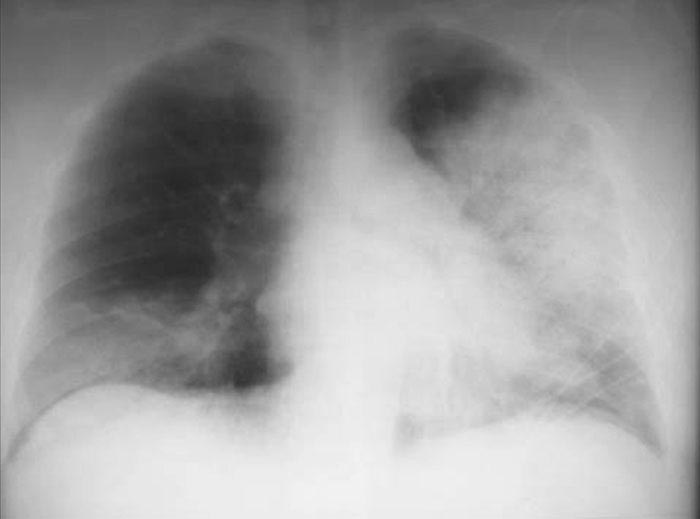

Modalidad de ventilación mecánica en el síndrome de distress respiratorio agudo

27 septiembre 2017

Una estrategia con reclutamiento pulmonar y PEEP titulada tuvo mayor mortalidad a los 28 días que la modalidad estándar de ventilación con PEEP baja. JAMA, 27 de septiembre de 2017